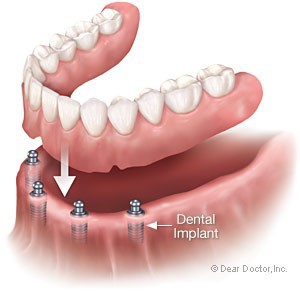

دیباچه ای بر شناخت ایمپلنت های دندانی

به طور کلی ایمپلنت به معنی "کاشت" یک عضو مصنوعی است که جایگزین یک بخش از دست رفته بدن می شود که نوع دیگری از ایمپلنت ها ، ایمپلنت های دندانی می باشد که از جنس تیتانیوم بوده و جایگزین ریشه دندان از دست رفته شده و درون استخوان و لثه قرار می گیرد و به دو نوع پیچ شونده و سمان شونده وبه دو فرم tissu level و bone level تقسیم می شوند.

به یکپارچگی ایمپلنت با استخوان فک را اسئواینتگریشین می گویند که عوامل هایی مانند دیابت کنترل نشده ، لوسمی یا همان فعالیت غیر عادی غدد پاراتیروئید ، افراد مبتلا به سرطان تحت شیمی درمانی یا فیزیوتراپی ، خانم های باردار تا پایان ماه سوم بارداری ،افراد مبتلا به نرمی استخوان ،افراد مبتلا به بیماری های کلیوی شدید و هچنین افراد وابسته به سیگار و الکل و ... مانع از این امر یکپارچگی فیزیولوژیکی استخوان و ایمپلنت های دندانی می شوند .

در چه مواردی از ایمپلنت استفاده می شود:

فاصله بین دندانهای جلو در اثر از دست رفتن یک دندان بطوری که دندانهای مجاور آن طبیعی باشند.

از دست رفتن دندان می تواند به دلیل پوسیدگی، بیماری لثه و یا تصادفات باشد. اگر دندان در منطقه زیبایی باشد علاوه بر زیبایی سلامتی دندان نیز متاثر می شود. فاصله طولانی بی دندانی باعث رویش دندانهای فک مقابل به این فاصله و جابجایی دندانهای بالا و پایین و از دست رفتن اکلوژن مناسب می شود. عمل جویدن نیز متاثر شده و مفاصل فک پایین در طولانی مدت دردناک می شود.

تقسیم بندی درمانهای متکی بر ایمپلنت دندانی

الف: بصورت فیکس(سیمان شونده یا پیچ شونده)

1- بازسازی یک تاج دندانی

2- بازسازی یک تاج وبخشی از ریشه

3- بازسازی یک تاج وریشه ومقادیری از لثه

ب: بصورت متحرک

1- پروتزهای متحرک متکی بر ایمپلنت که ساپورت به صورت کامل فقط از ایمپلنت تامین می گردد.

2- پروتزهای متحرک متکی بر ایمپیلنت که ساپورت هم از ایمپلنت وهم از بافت تامین می گردد.